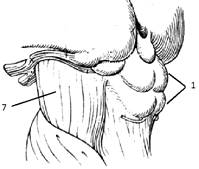

Сердце. Топография, внешнее строение

Различают три поверхности сердца:

грудино-реберную, диафрагмальную, легочную, а также правый край сердца.

Грудино-реберная поверхность выпуклая, касается грудной стенки только областью

верхушки. Диафрагмальная поверхность целиком прилегает к диафрагме, эта

поверхность сердца уплощена. Легочная поверхность, соответствующая сердечному

вдавлению левого легкого, выпуклая. Правый край входит в состав стенки правого

желудочка. На поверхности сердца находятся передняя и задняя межжелудочковые

борозды, охватывающие сердце спереди и сзади, и поперечная венечная борозда,

расположенная кольцеобразно.

В грудной полости сердце занимает косое

положение и обращено широкой частью – основанием кверху, назад и вправо, а

узкой – верхушкой вперед, вниз и влево, на две трети оно располагается в левой

половине грудной полости.

Границы сердца сверху проецируются во втором

подреберье, справа выступают на 2 см за правый край грудины, верхушка сердца

залегает в пятом левом межреберье на 1 см. кнутри от левой среднеключичной

линии. Положение границы сердца изменчивы и зависят от возраста, пола,

конституции человека и положения тела.